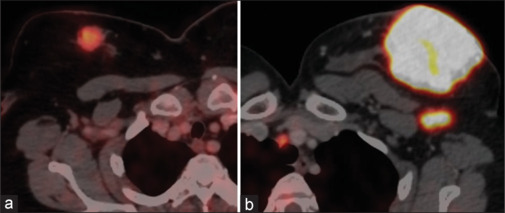

Results: Sixty-five female patients met the inclusion criteria, and the majority of them presented with intraductal carcinoma. The median value (interquartile range [IQR]) of the Ki-67 index was 40% (IQR: 50%). The primary breast tumor showed median (IQR) of SUVmax, SUR, TLG, and MTV of 10.3 g/mL (7.2), 3.7 (2.9), 102.9 g.cub/mL (184.7), and 16.2 cm3 (25.4), respectively. A significant correlation was noted between all the metabolic parameters studied and the Ki-67 index. In subgroup analysis, a significant difference was noted in all the metabolic parameters between the subgroups of the Ki-67 index ≤25% versus >25%.

Conclusion: Metabolic parameters on 18F FDG PET/CT show a promising role in the determination of the status of proliferation marker Ki-67 index in carcinoma breast.